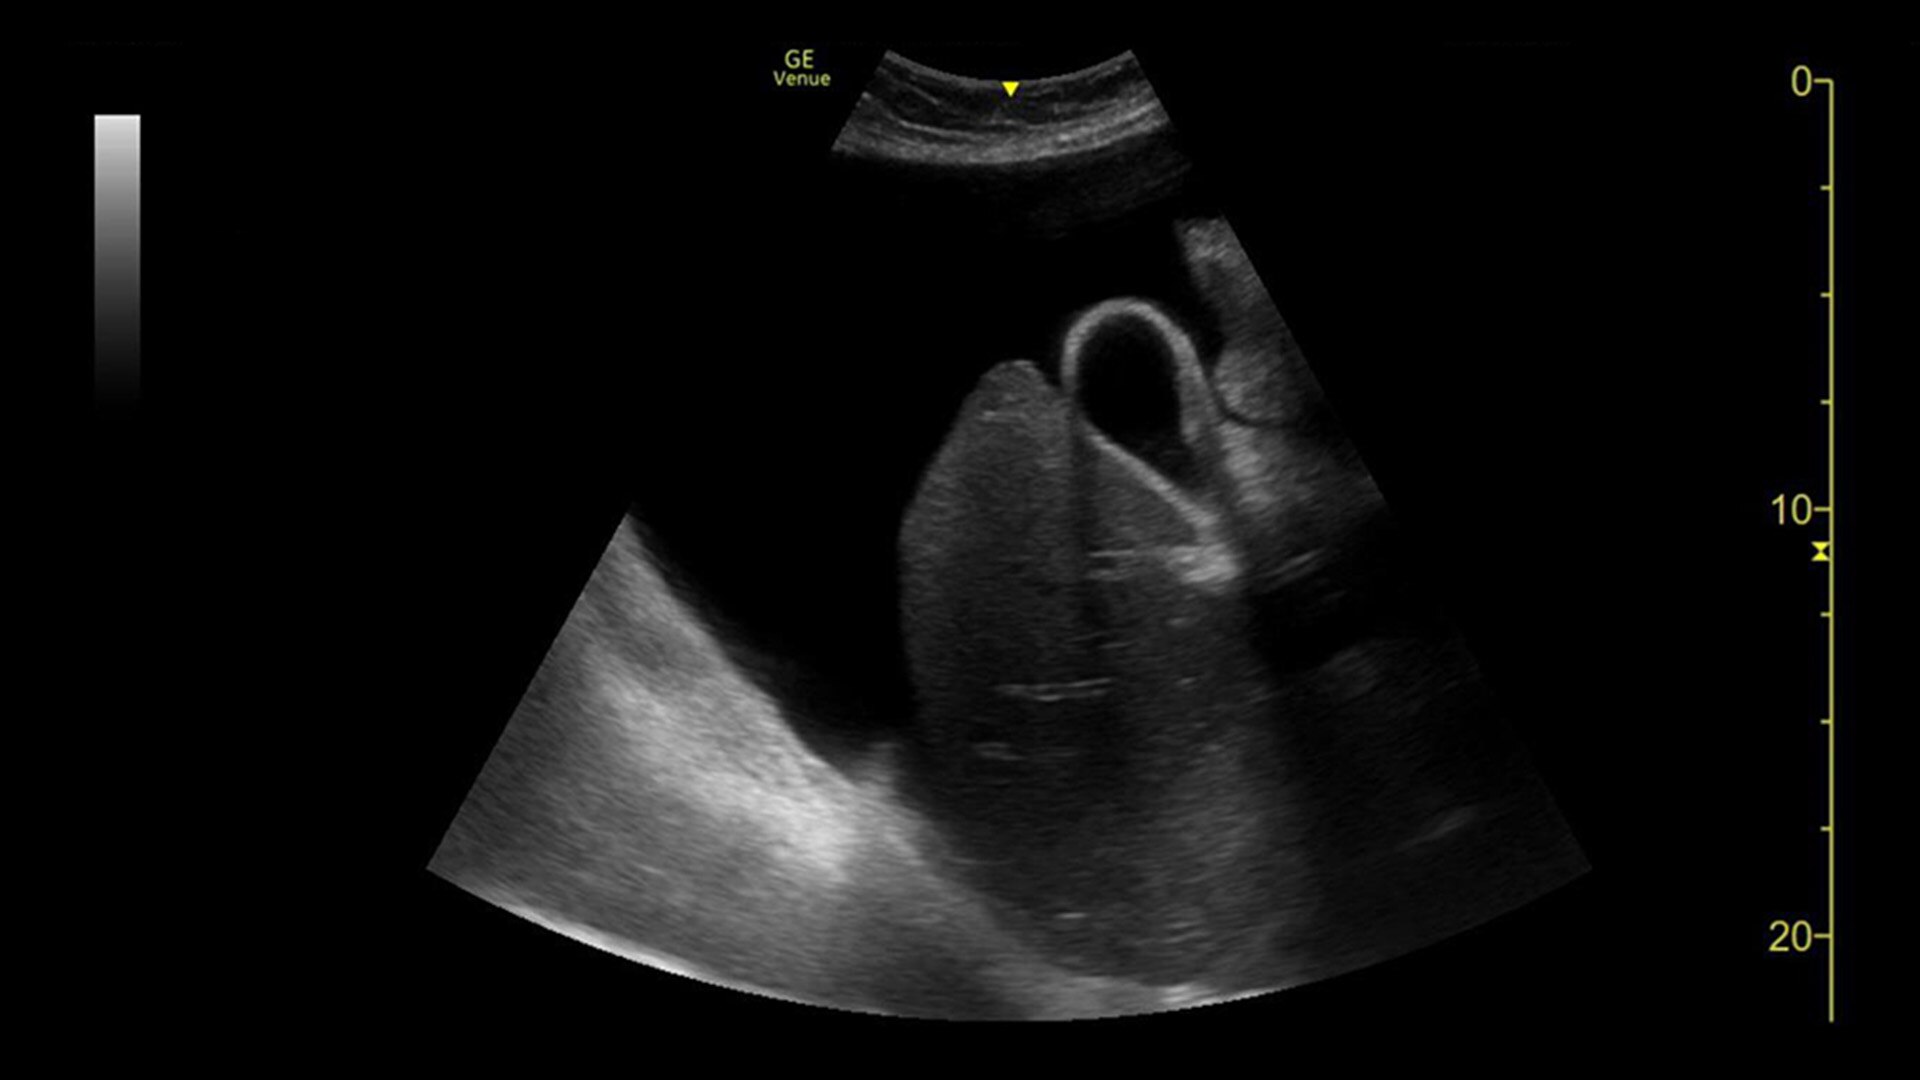

LUNG SWEEP

Visualize the entire lung and make your diagnosis

Lung Sweep, a rapid visualization tool, provides a dynamic panoramic view of the entire lung. Automatically activated at the start of each sweep when the probe is tapped on the body, Lung Sweep is deactivated at the end of each sweep when the probe is lifted– there is no need to touch the screen. The Auto B-lines tool can be used in conjunction with Lung sweep to highlight B-lines over the entire panoramic view and display the frame with the most B-lines per rib space.